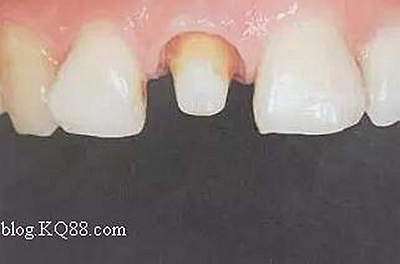

在操作的過(guò)程中要注意無(wú)菌操作,保證纖維樁的無(wú)菌狀態(tài)。推薦將樹(shù)脂核堆好之后再截?cái)嗬w維樁,而不是截?cái)嗪笤僬辰印H缦聢D:

10、排齦精修